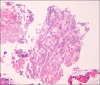

A 47-year old man visited our hospital because of purulent sputum for 3 months. Chest X-ray showed destruction of both the upper lungs, and bronchoscopy revealed inflammatory change with whitish plaque on the left main bronchus through upper division of the left upper lobe. Tracheobronchial aspergillosis (TBA) was finally diagnosed as a result of histologic and microbiologic examination. However, he went abroad without medication before the diagnosis was made and visited again 10 months later. Follow-up bronchoscopy showed complete regression of the previously noted endobronchial lesion. We describe this case to consider the role of antifungal treatment in immunocompetent hosts, as well as to discuss a rare condition; TBA resolved spontaneously.